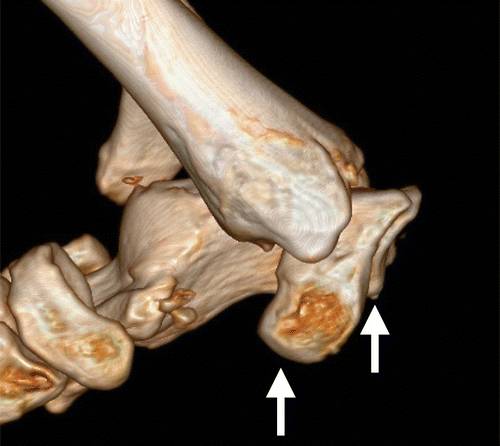

图13b后突骨折。 (a)右足的外侧X光片显示在距骨后方的小骨质碎片(箭头)。 (b)右脚的轴向CT图像显示后路过程骨折(箭头)以及粉碎的程度和程度。